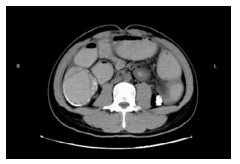

病例2,患者男,60岁。因“反复右上腹痛半月,加重2 d”于2022年8月29日来院急诊。入院查体:腹部膨隆,右上腹部压痛,无反跳痛。上腹部增强CT示结肠肝曲壁厚强化、管腔狭窄,考虑结肠肝曲恶性肿瘤并突破浆膜层,近段升结肠内容物堆积伴梗阻、肠壁肿胀伴扩张,病变周围及腹膜后多发淋巴结转移,肝多发转移。WBC12.7×109/L, N 81.1%。血CEA 29.05 ng/mL,CA19-9 39.07 IU/mL,CA125 41.21 U/mL。8月30日予行结肠镜下肠道支架置入术,检查进镜至结肠肝曲,见肠腔肿物堵塞,肠腔狭窄内镜无法通过,取病理活检后,沿导丝置入肠道非覆膜金属支架一枚(图 3)。患者肠道支架置入当天即感腹痛和腹胀症状消失,急性肠梗阻症状明显缓解。肠镜病理提示:结肠肝曲腺癌。经多学科讨论后于9月3日开始行XELOX方案术前转化治疗。目前患者病情平稳,规律行术前转化治疗中。

| 图 3 结肠肝曲癌伴肠腔狭窄行肠镜下结肠支架置入术 |